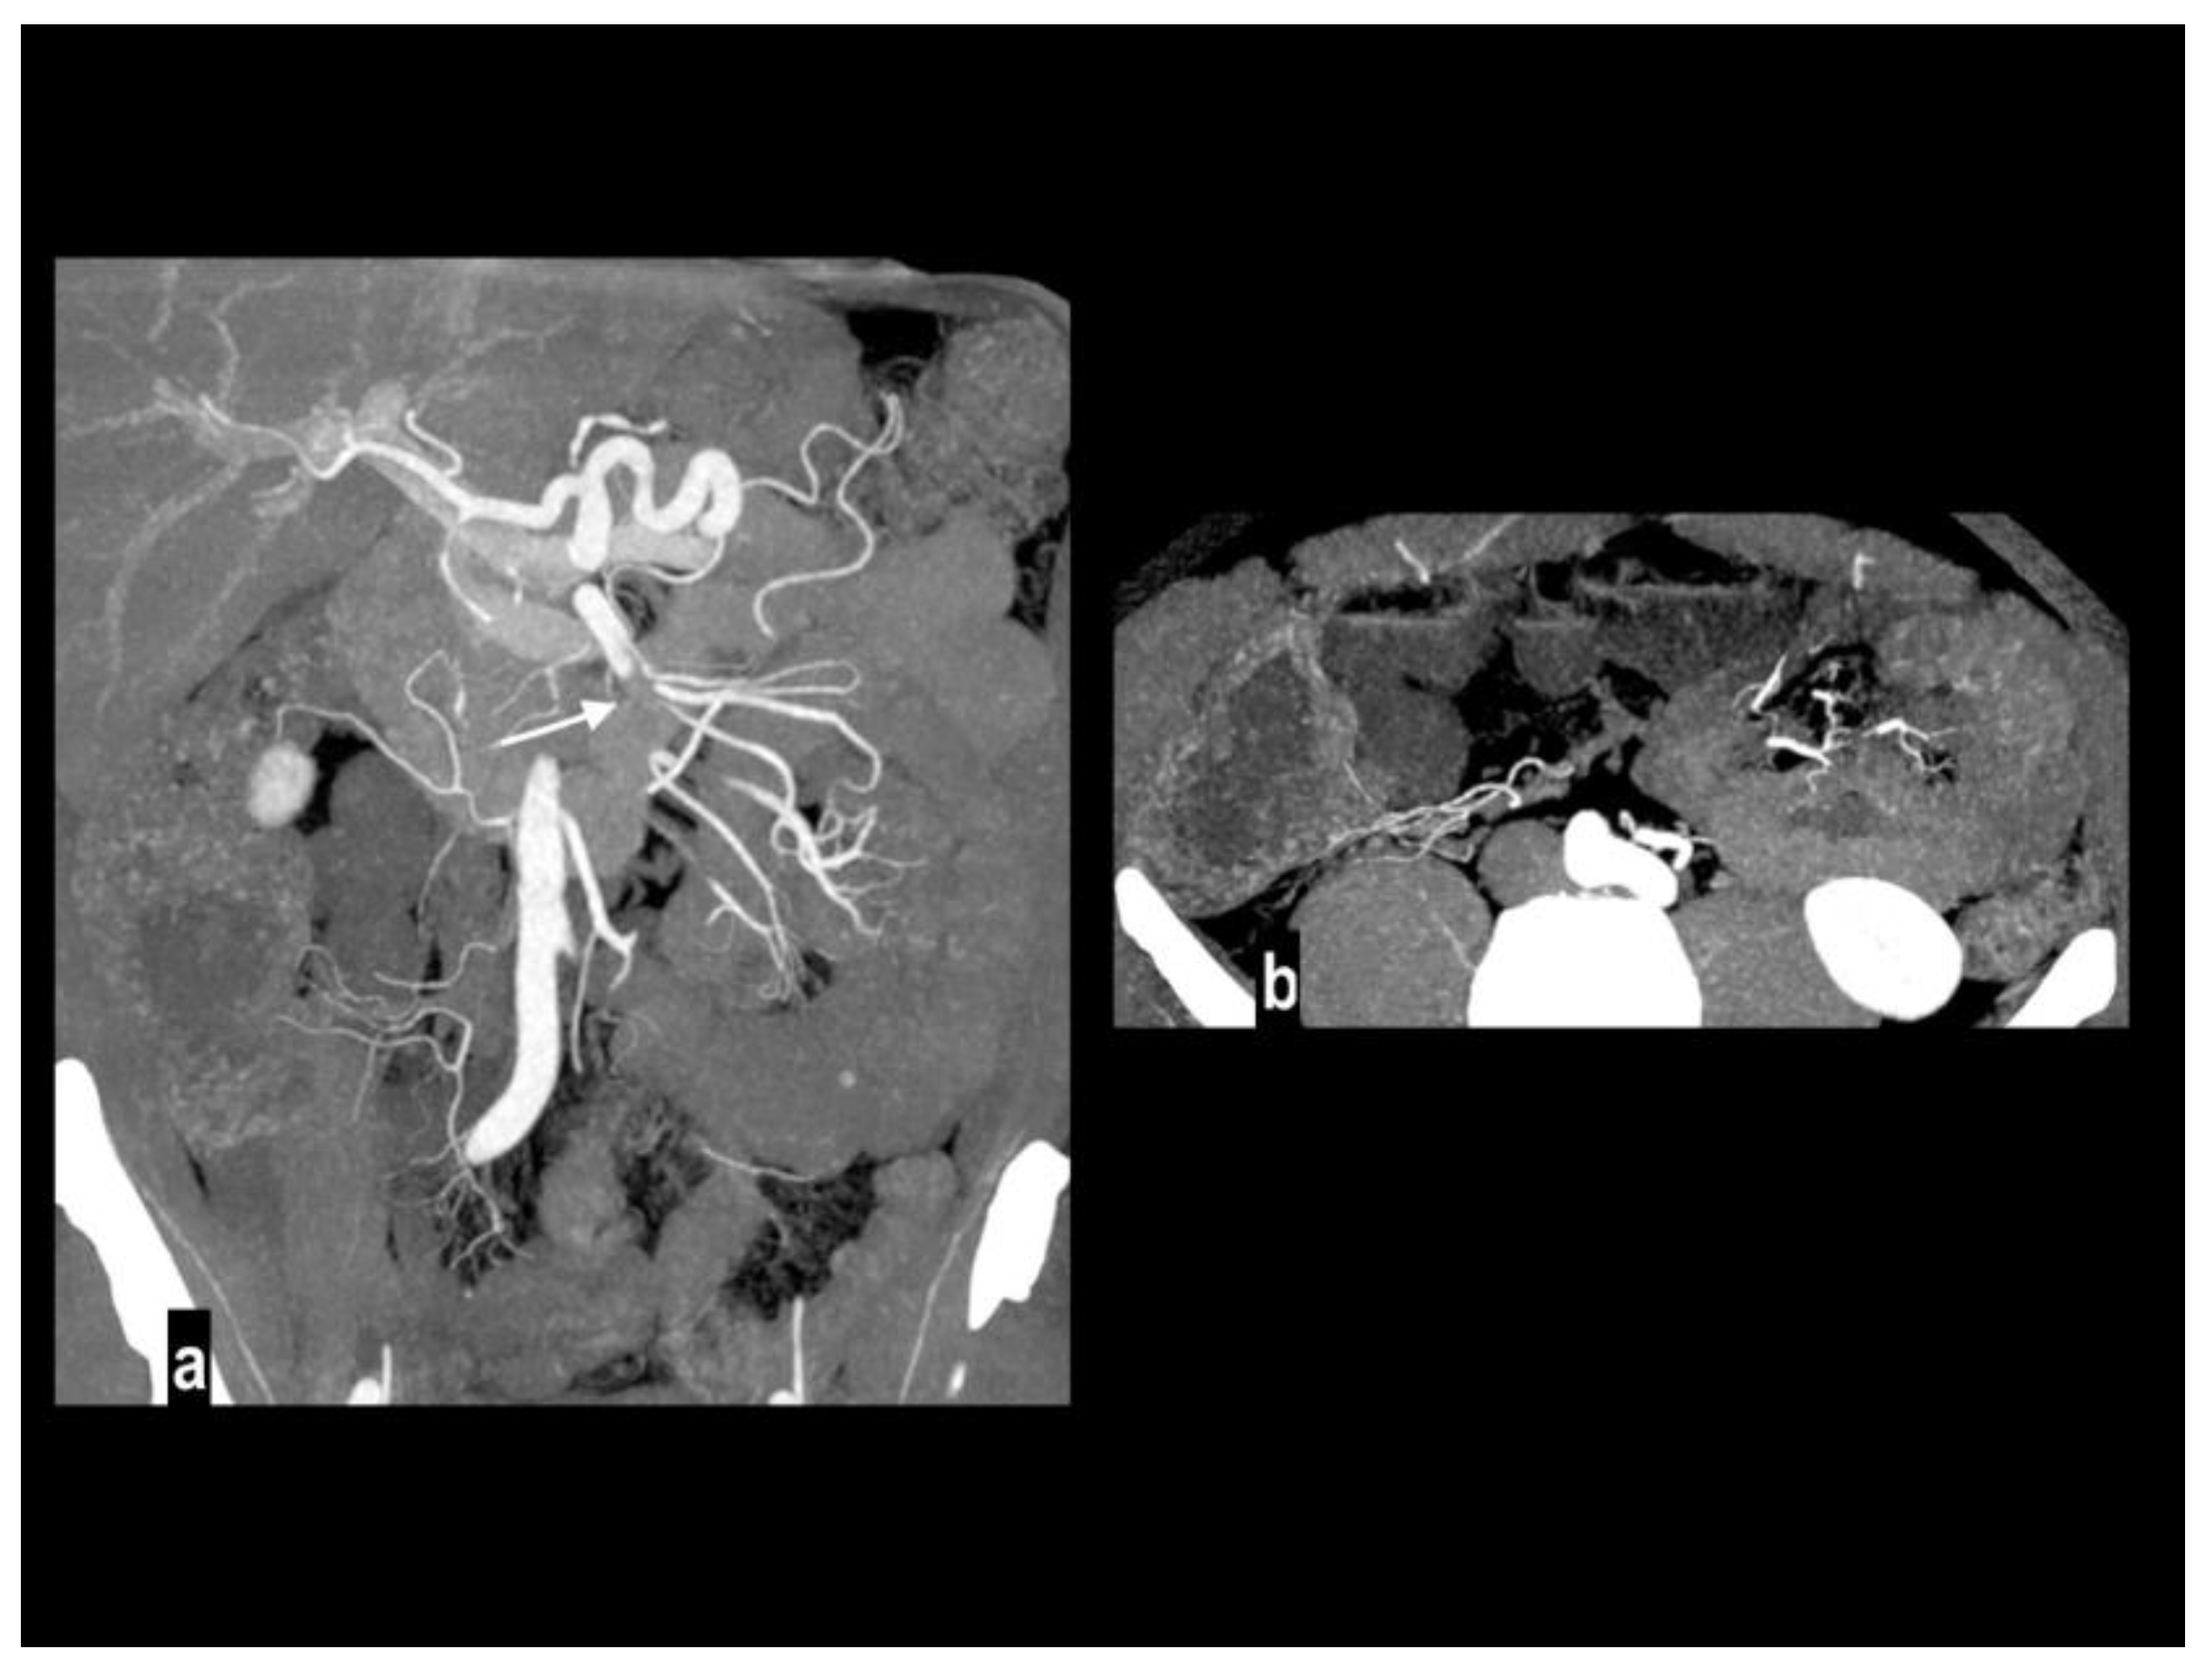

Figure 2. Embolic mesenteric ischemia in a 57-year-old man with atrial fibrillation. Coronal MIP arterial image (figure 2a) showed embolic occlusion of middle SMA (arrow), with preserved jejunal arteries enhancement and right colonic vessels collateralization. Hypoenhancing wall was appreciated only in distal ileus (figure 2b).

Preprints 106216 g002